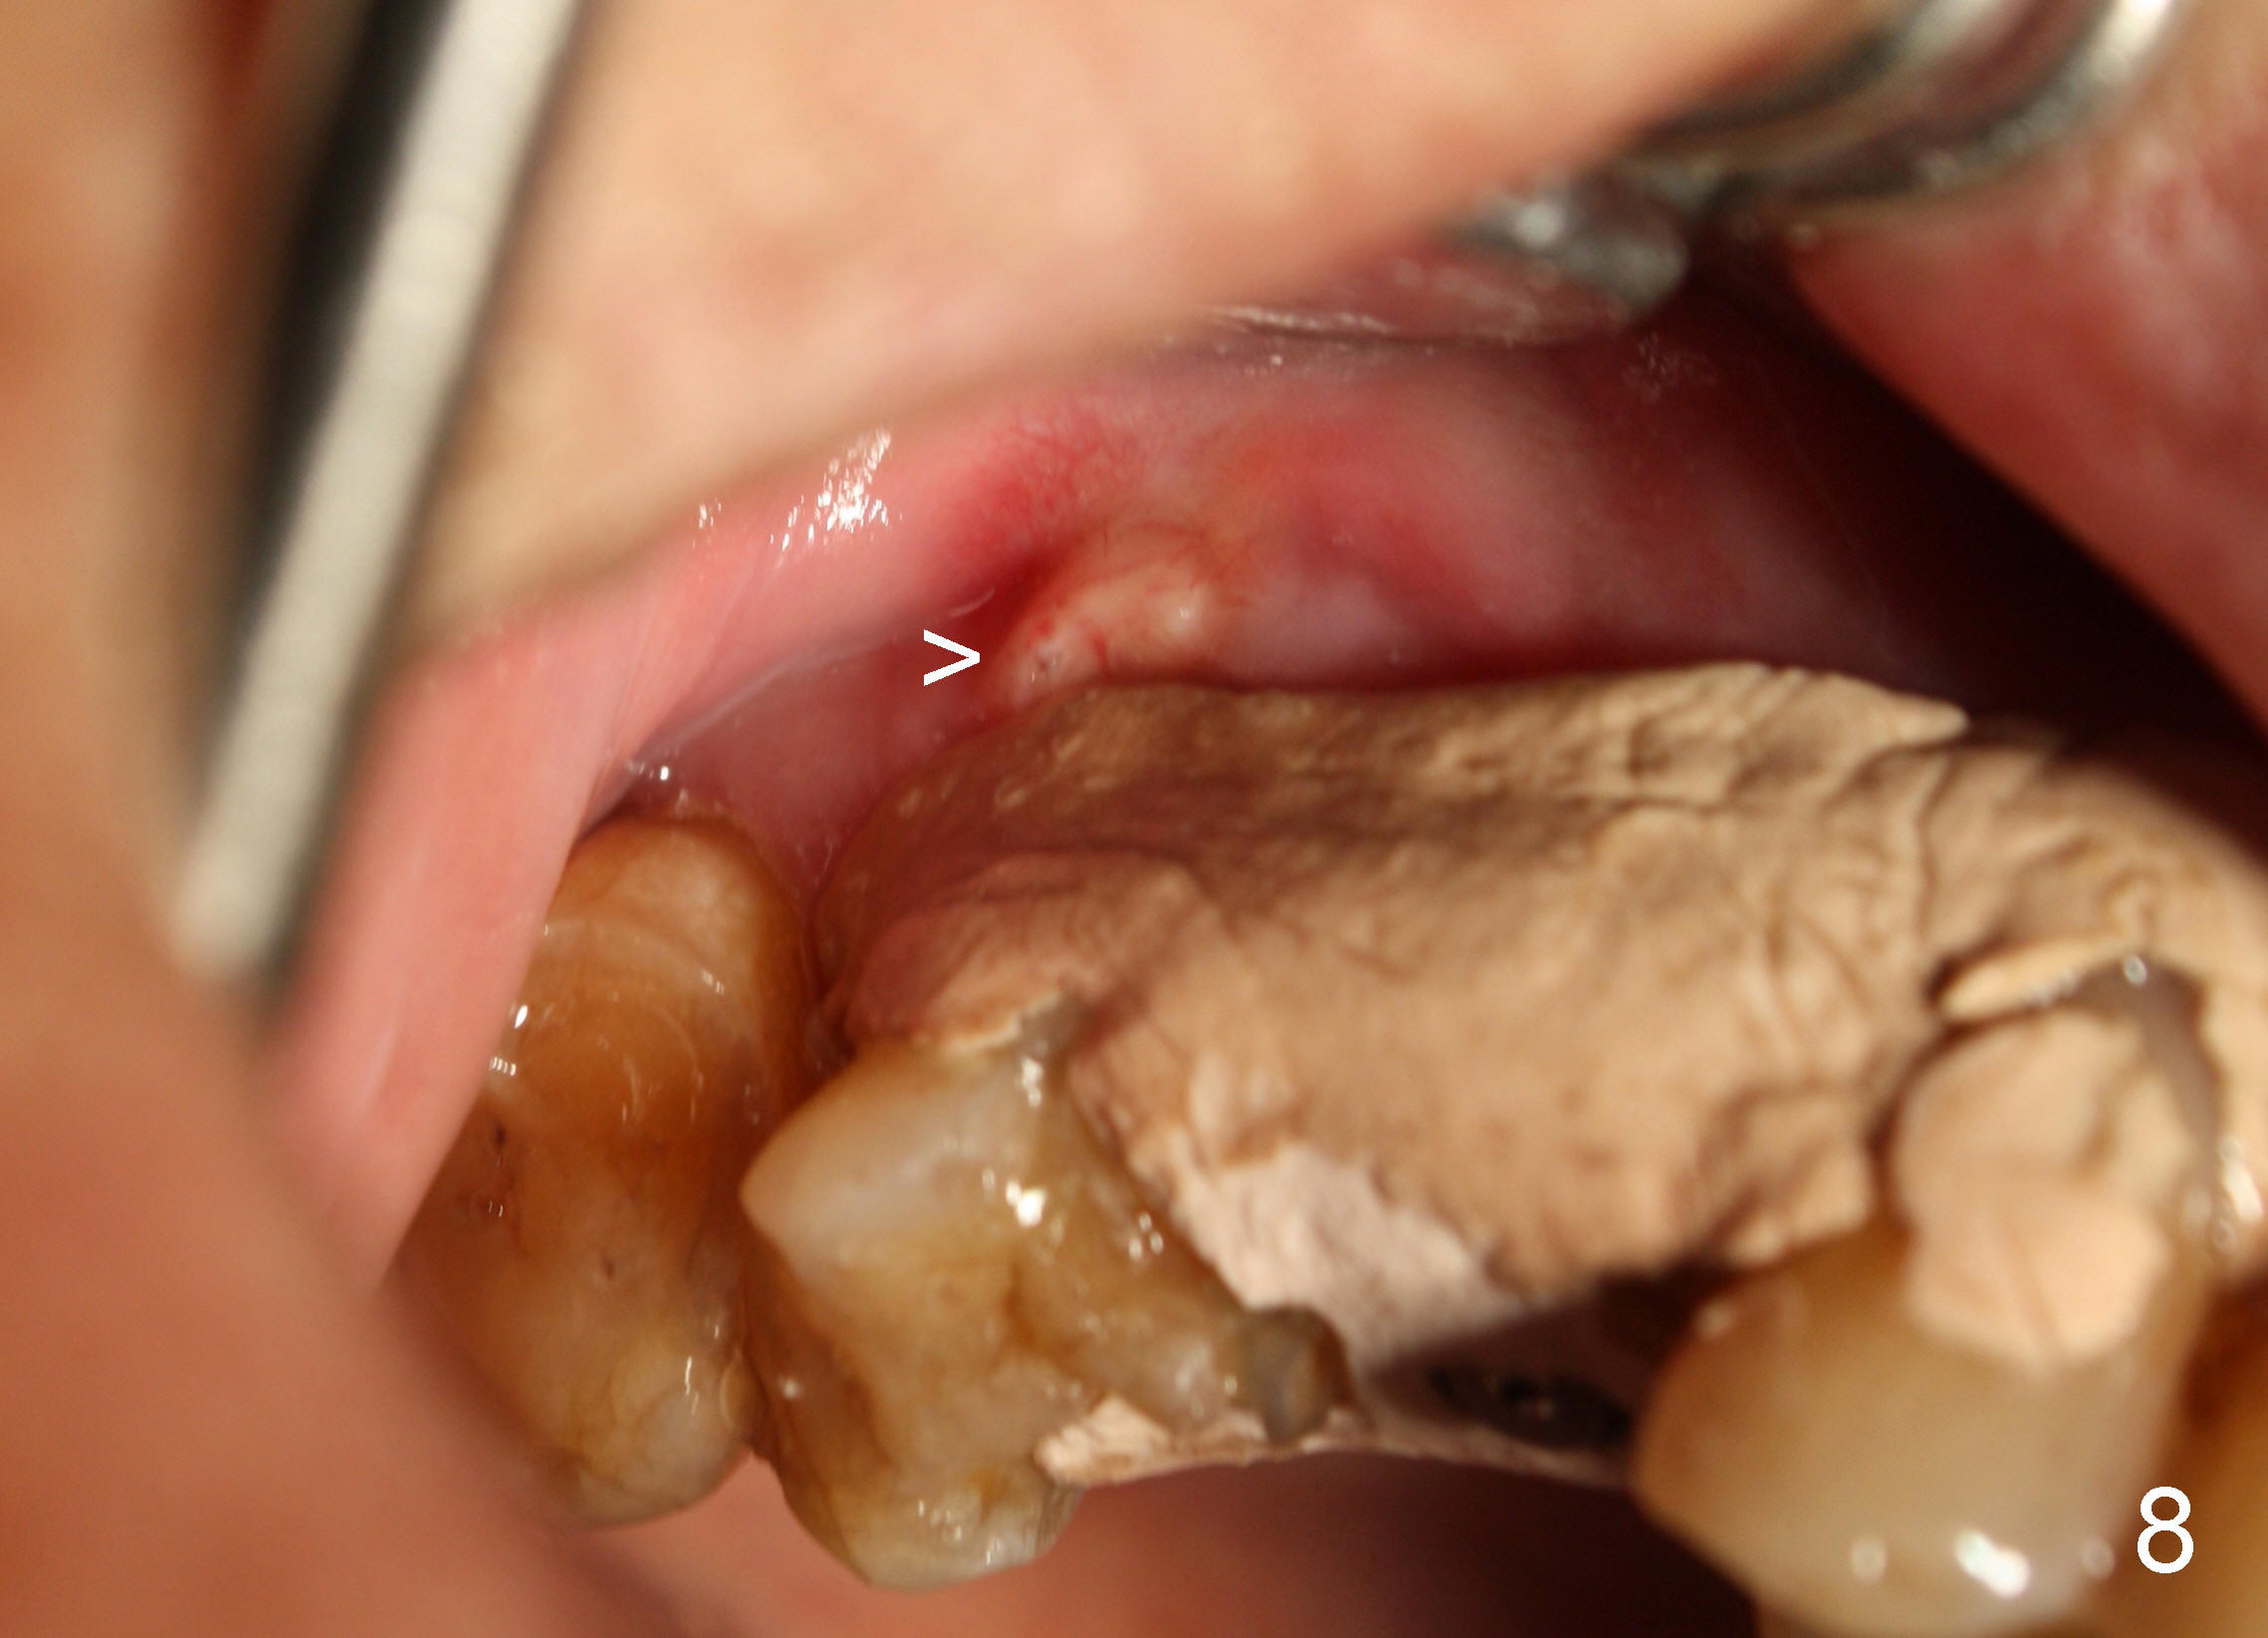

A 72-year-old man is a bruxer with #3 cusp fracture with chronic periapical radiolucency (Fig.1 *) and #4 acute crack.  It appears reasonable to take care of emergency (#4 extraction and immediate implant (Fig.3-7: 4.5x20 mm, 45 Ncm)) followed by root canal therapy or extraction for #3.  Eight (Fig.8) and 14 (Fig.9-11) days postop, the patient is doing fine and the wound heals normally.  But he does not agree any treatment for #3, since it is asymptomatic in spite of a fistula associated with the tooth (Fig.8,9 >).  Three months postop, the patient is still asymptomatic and is ready for #4 restoration since the tooth #28 cracks.  Follow-up PA shows the persistent distal gap (Fig.12 >, as compared to Fig.4), accompanied with crestal bone resorption (*).  Clinically the implant has mild mobility and light tenderness. The patient still refuses #3 treatment. It appears that the implant has failed to osteointegrate.  In brief, do not place an immediate implant next to active infection.